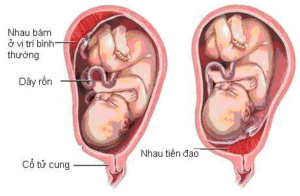

Rau tiền đạo khi mang thai: Nguyên nhân, dấu hiệu và cách điều trị

Rau tiền đạo khi mang thai là tình trạng nguy hiểm khi bánh nhau bám ...